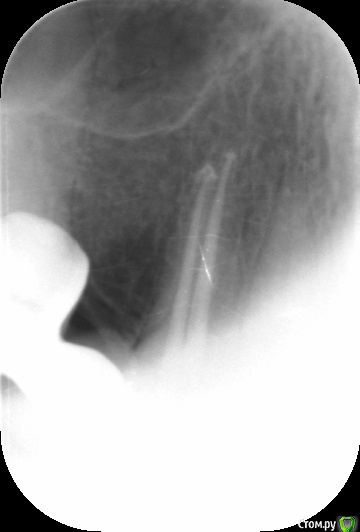

Татьяна-spb Опубликовано 14 июля, 2015 Автор Поделиться Опубликовано 14 июля, 2015 Спасибо за комментарий.Вот снимок 6-ки(был глубокий кариес) с лекарством в каналах .Подскажите,пожалуйста,на нижнюю челюсть менее года тому назад одновременно с верхней тоже была поставлена металкерамика(5,6 слева) и мост(4,5,6 отсутствует,7 справа)три зуба (6 слева,5 и 7 справа-опорные)не перелечивались,каналы запломбированы не до конца,формулировка-"простояли же они под старыми коронками не один год , а может и не побеспокоят".Сейчас обнаружился еще периодонтит на 2 корнях нижней 6-ки слева.Нужно ли было перелечивание? Ссылка на комментарий